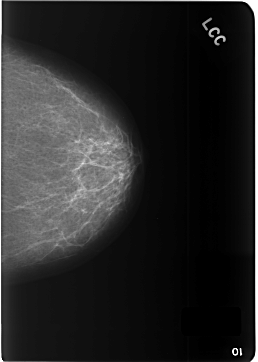

Volume: cancer_09 Case: C-0342-1

C_0342_1.LEFT_CC

LEFT_CC LINES 5784 PIXELS_PER_LINE 4120 BITS_PER_PIXEL 12 RESOLUTION 50 NON_OVERLAY